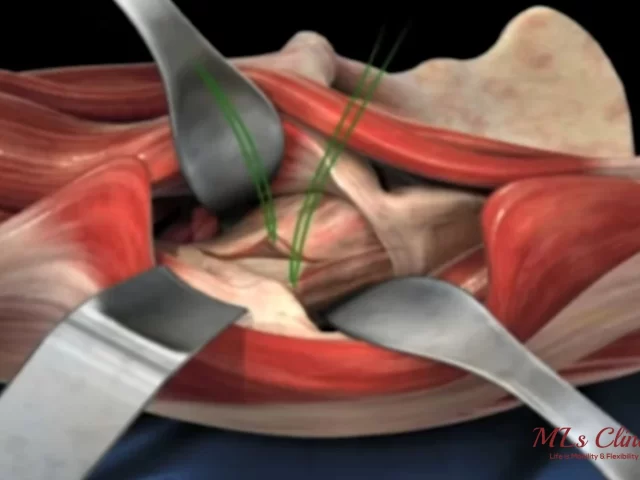

Hip replacement- Direct Anterior Approach(DAA) vs MIS Posterior Approach

Have you been advised to get your hip replacement surgery done? Are you worried about which surgical approach you should...